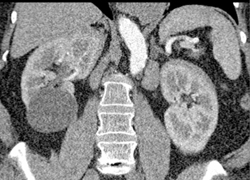

Diagnosis

Renal Cyst